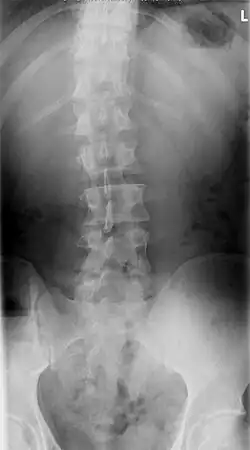

Men onderscheidt een S-vormige scoliose met twee bochten en een C-vormige scoliose met één bocht. Een S-scoliose benoemt men naar de convexe (bolle) kant van de grootste bocht; bijvoorbeeld een S-vormige thoracale scoliose, rechts convex van 35 graden. De wervelkolom is meestal tevens om zijn as gedraaid, men spreekt dan van een torsiescoliose, waardoor een bochel (gibbus) ontstaat. Hoewel het een ingewikkelde driedimensionale vervorming betreft, kan men op een gewone voor-achterwaartse röntgenfoto de zijdelingse verkromming goed zien als een C-vormige of een S-vormige slinger in de ruggengraat die eigenlijk een rechte lijn behoort te zijn. Een structurele scoliose zal meestal gepaard gaan met een draaiing, een torsie; ook een bijkomende voorovergebogen houding (kyfose), een holle rug (lordose) of beide komen vaak samen met de scoliose voor. Belangrijk is of de scoliose in evenwicht is, dat wil zeggen of het zwaartepunt van het lichaam tussen de voeten valt. Als de wervelkolom van de patiënt een S-vormige bocht heeft, kan zich op borsthoogte een convexe bocht naar rechts bevinden en op lendenniveau een convexe bocht naar links. Meestal heffen de bochten elkaar op. Indien dit niet het geval is, bestaat er een grote kans op verergering.

Een niet-structurele scoliose kan worden gecorrigeerd. Op foto's is de scoliose dan niet meer te zien.